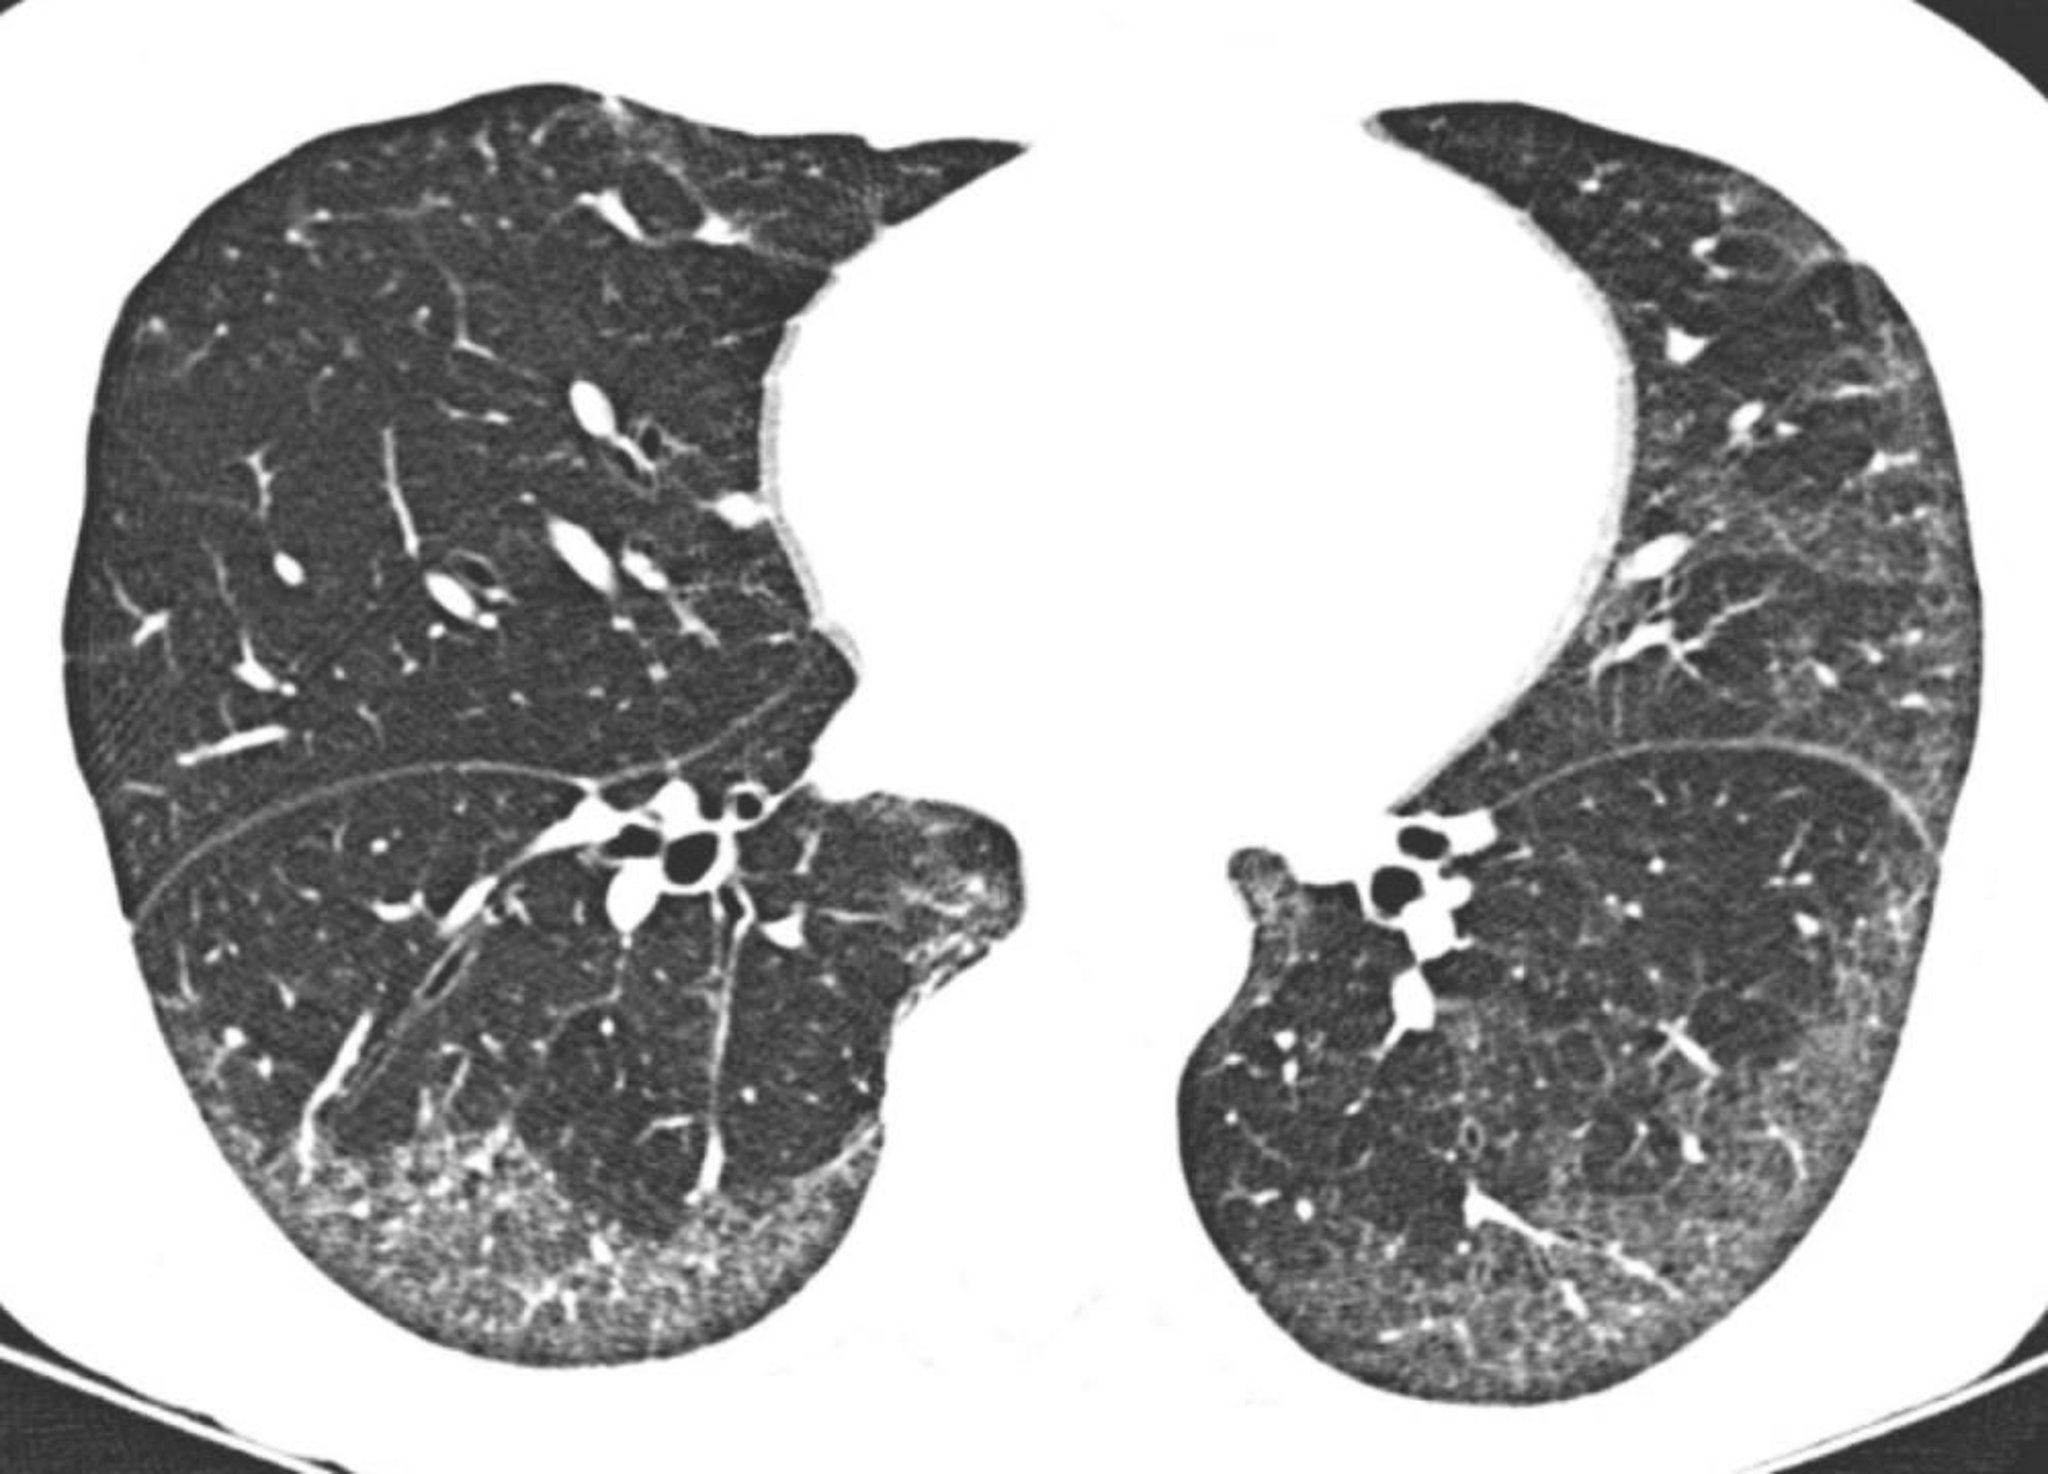

Идиопатическая неспецифическая интерстициальная пневмония

На снимках КТ высокого разрешения показывано преимущественно субплевральное затемнение по типу «матового стекла», а также затемнение по типу «матового стекла» в области основания головного мозга. Связанная с легким щель непосредственно под плевральными поверхностями типична для неспецифической интерстициальной пневмонии.

Image courtesy of Harold R. Collard, MD.